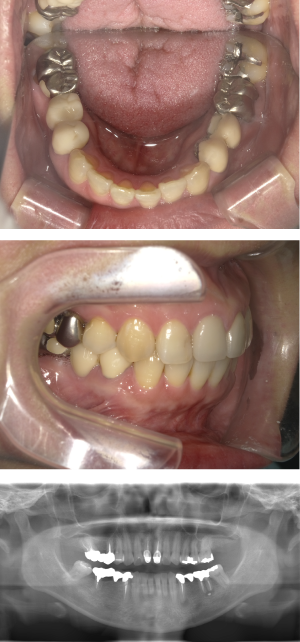

70代 女性 インプラント治療(GBR)

| 年代・性別 | 70代・女性 |

|---|---|

| 主訴 | 抜歯適応になってしまった所にインプラント治療希望。 |

| 部位 | 右上3・5(右上345のブリッジ)、右下6・7 左上4・6(左上456のブリッジ)、左下6・7 |

| 治療期間 | 約14ヶ月 |

| 費用 | ¥3,740,000(税込) |

| 副作用・リスク |

|